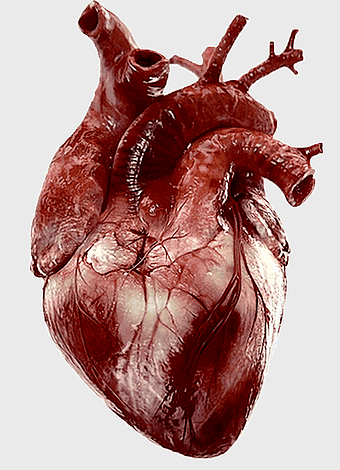

human heart anatomy, cardiac muscle illustration, circulatory system model, heart health visual, cardiovascular organ diagram, medical heart image, visceral structure depiction -

512x512px

Heart Anatomy Drawing, human heart illustration, human anatomy art, organ depiction, cardiovascular system, medical illustration, anatomical sketch -

1370x870px

human heart anatomy, superior vena cava illustration, systemic circulation diagram, heart rate visual, cardiovascular system study, medical organ depiction, human body organ reference -

961x789px

human heart anatomy, cardiovascular system illustration, medical heart diagram, heart organ structure, human body organ visuals, anatomical heart drawing, heart health -

1120x1440px

human heart diagram, cardiovascular system anatomy, blood vessel chart, free body diagram, circulatory system illustration, medical organ visualization, human anatomy study -

1024x1024px